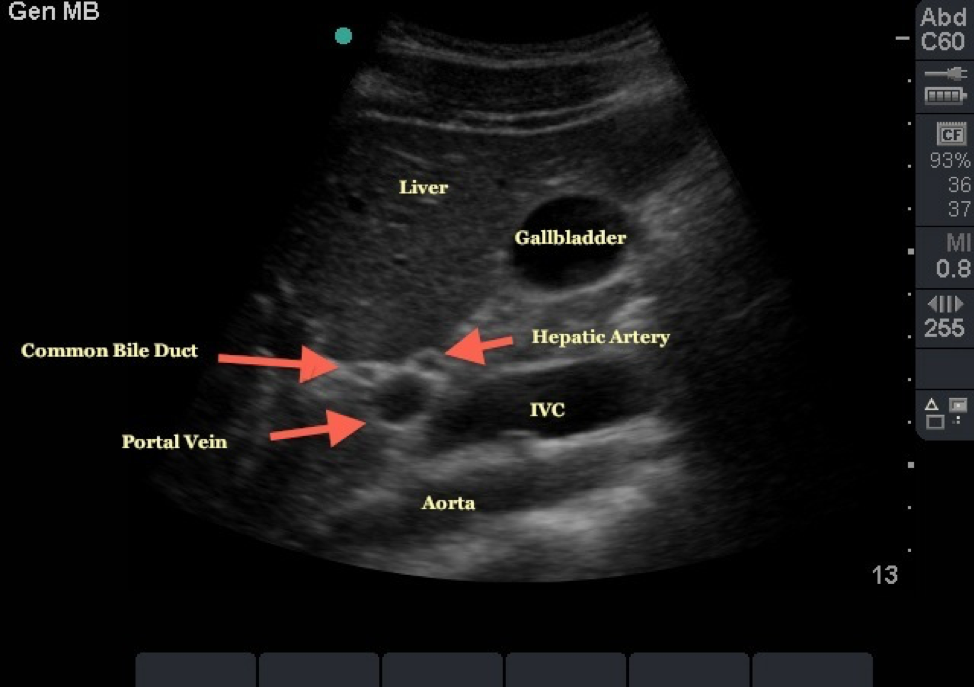

What plane is this

Transverse right lobe of liver

What plane is this?

Sagittal or long